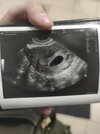

Jest już ciałko żółte ale takie małe że jeszcze nie da się zmierzyć. Umawiam się zaraz na 1,2 grudnia a w przyszłym tyg na USG pod koniec miesiąca. Ale wszystko dobrze. Mam już swoją kropkę widzialną 🥰🥰🥰

Załączniki

• 1637655824736116634058307355962.jpg

1637655824736116634058307355962.jpg

975,1 KB · Wyświetleń: 88